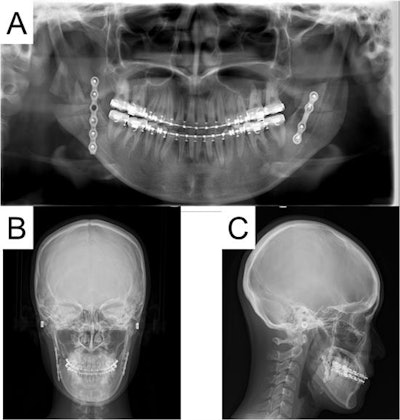

Finally, clinicians put back the removed distal cortical bone. A monocortical titanium plate with five screws was used to fix the right side, and a plate with four screws was used to fix the left side. Surgeons checked her mouth opening and occlusion after they removed the wires between her upper and lower jaws and then closed the wound. X-rays taken after the procedures showed no abnormalities.